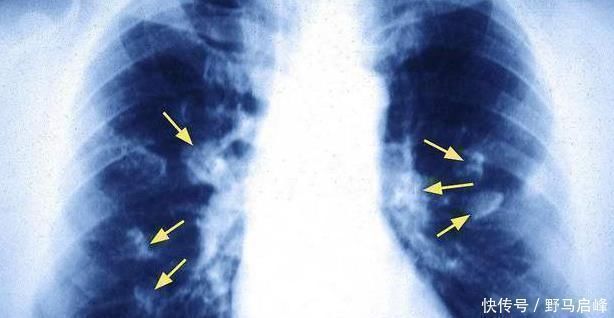

据我们所知,癌症的治疗能力不是很高,但是与中后期患者相比较。如果癌症早期发现线索,能够采取适当的措施和积极的治疗,癌症状况仍然得到良好的控制,甚至有些人已经扭转了癌症。现在很多朋友都没有定期体检的习惯,这也很容易错过早期发现癌症的一部分。对于得癌症的肺癌,任何人都不太陌生。肺癌也在初期消失了。你身体出现这四种症状的时候,可能是肺癌在路上的信号,不行!

■肺癌来临前,身体也是蜘蛛网痕迹,注意到这四种身体表达!